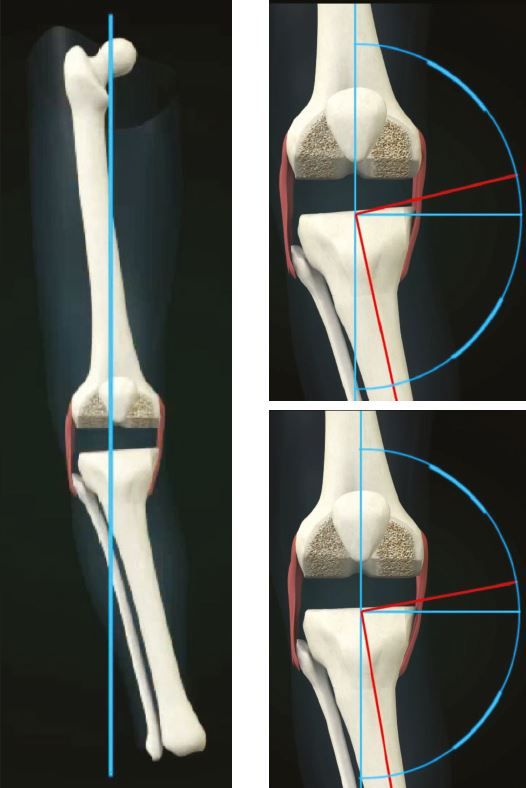

4. Hindfoot valgus (flat foot) needs to be recognised7 (Fig 7)

If extra-articular deformity (EAD) is >20 degrees, close to the joint, and resection likely to damage LCL attachment or if the distal tibial axis falls outside of tibial plateau, then EA osteotomy may be required.(Figs 4-6)